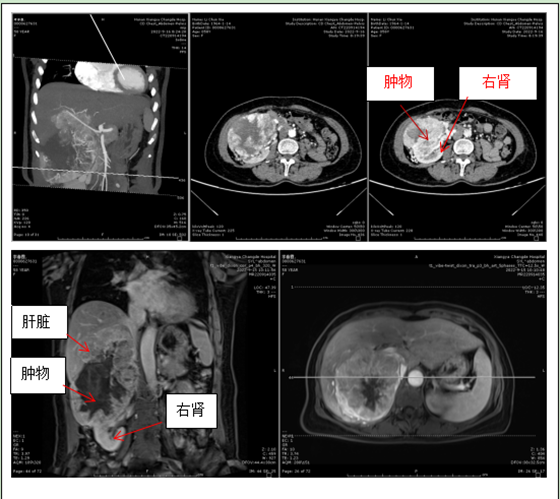

李阿姨入住普外科后,科室迅速对李阿姨进行相关检查,CT和磁共振均确定可能是巨块型肝癌。李阿姨没有乙肝背景,不喝酒,无脂肪肝,无肝硬化,肝癌缺乏诱因,且李阿姨的肿瘤标志物均正常,无疑使诊断变得扑朔迷离。仔细阅片可知肿物上顶肝脏、下压右肾,与肝肾关系均密不可分,李阿姨高血压多年,服用硝苯地平片降压,但血压控制欠佳,一度怀疑肿瘤是否来源肾脏或者肾上腺,因此进一步进行了相关检验予以排查。

针对李阿姨病情,湘雅常德医院普通外科团队在肖广发教授带领下,为她做了充分的术前检查评估,组织全科进行疑难病例讨论,并请泌尿外科一起协助诊疗。经过详细讨论后,一致认为李阿姨腹腔内肿物有三个来源可能:其一,肝脏肿瘤;其二、右肾肿瘤;其三、腹膜后肿瘤。无论是何来源,肿物都存在手术切除可能。鉴于肿瘤巨大,与下腔静脉紧密粘连推挤,周边迂曲增粗血管非常多,紧贴第一肝门入肝血管,操作空间有限,手术方式可能采取右半肝切除+胆囊切除+右肾切除的多个脏器联合切除,手术难度、创伤极大。在征得李阿姨及其家属同意后,经过缜密规划和准备,手术按计划进行。